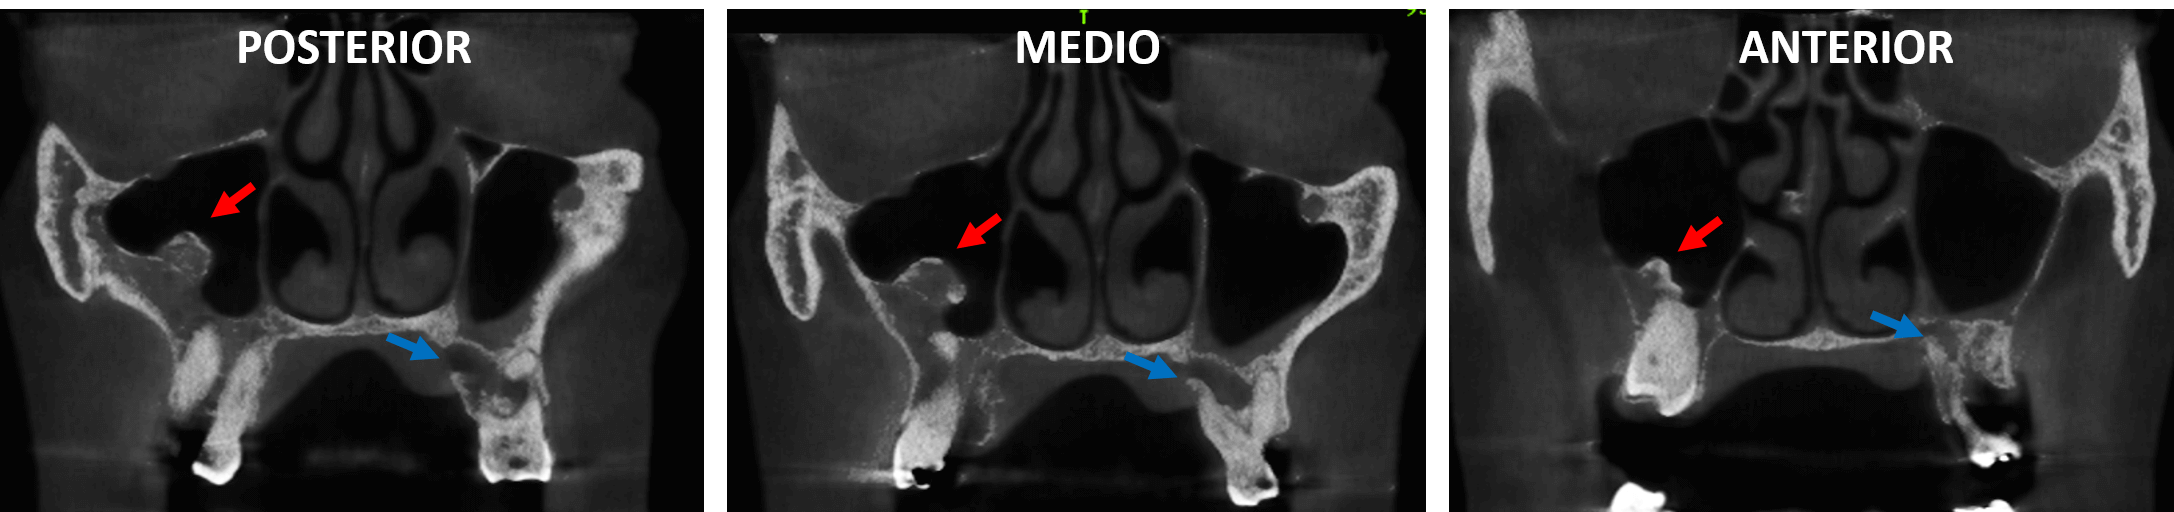

Fig.2

En cortes laterales (Fig.3) se observa la extensión anteroposterior de la estructura de densidad ósea localizada en el interior del seno maxilar (flecha roja), observando que presenta mayor densidad a la parte más superior, semejante a una cortical (cortes medial y medio) y que presenta su base entre las paredes basal y lateral (corte lateral).